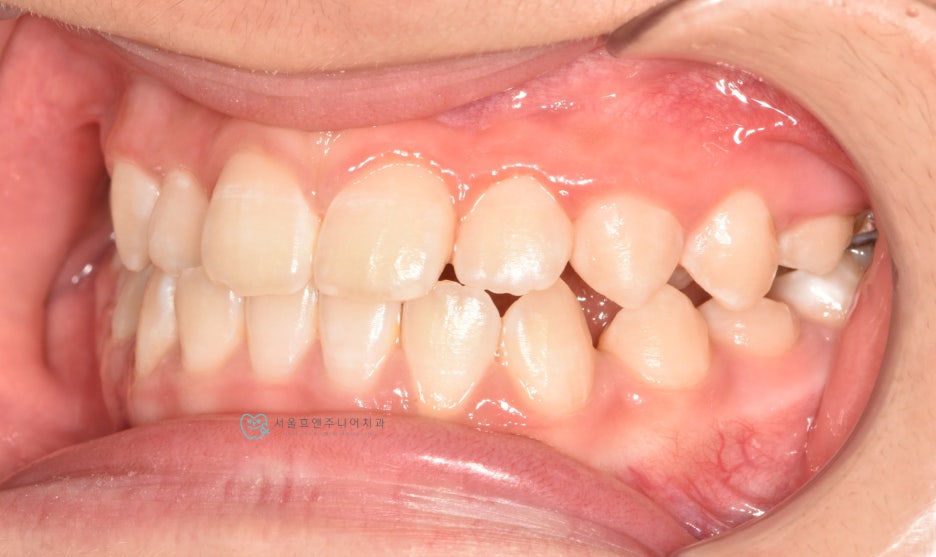

프리올소 착용 9개월 뒤

프리올소 착용 후 9개월 뒤 모습입니다. 앞니 반대교합이 수정되었습니다. 처음에 문제가 되고 있었던 아래앞니의 치은퇴축도 많이 개선되었습니다. 교합이 개선되어 치아의 위치가 바로잡히고, 치아에 무리한 힘을 더 이상 주지 않으니, 치은퇴축은 시간이 더 지나면서 점점 더 개선될 것으로 생각됩니다.